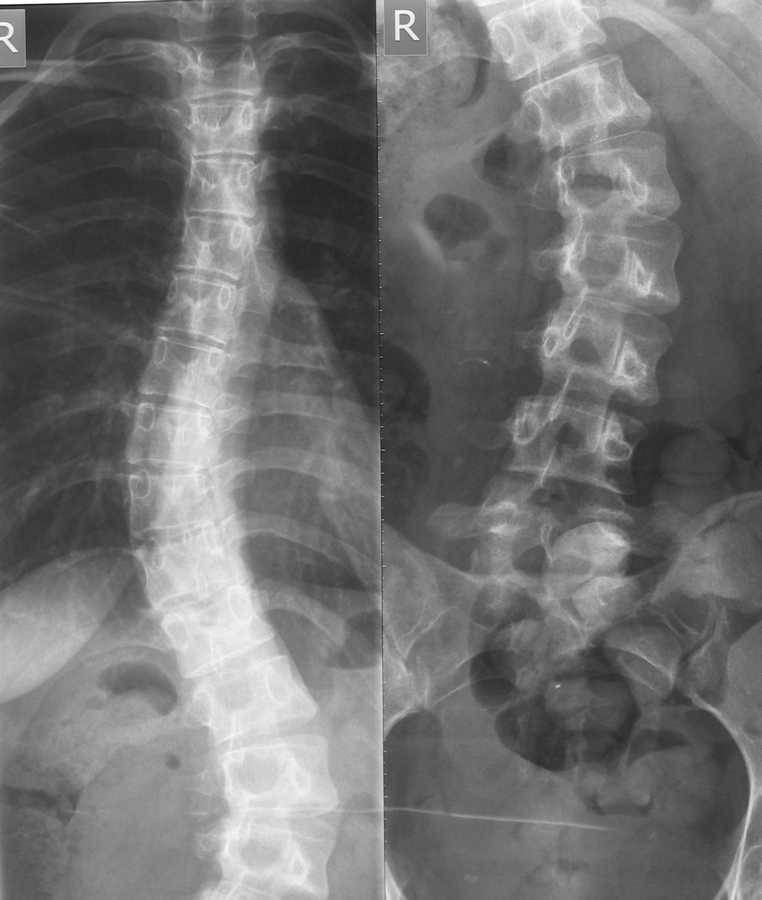

Здравствуйте уважаемые коллеги. Помогите разобраться в ситуации. Девушка 22 года, впервые выявлен сколиоз около 5 лет назад.

Получала несколько раз курс консервативного лечения. На данный момент ситуация видна на представленном снимке. Клинически проявляется только в косметическом дефекте, боли не беспокоят. имеет ли смысл устранять косметический дефект хирургически,если - да, то на какой базе?